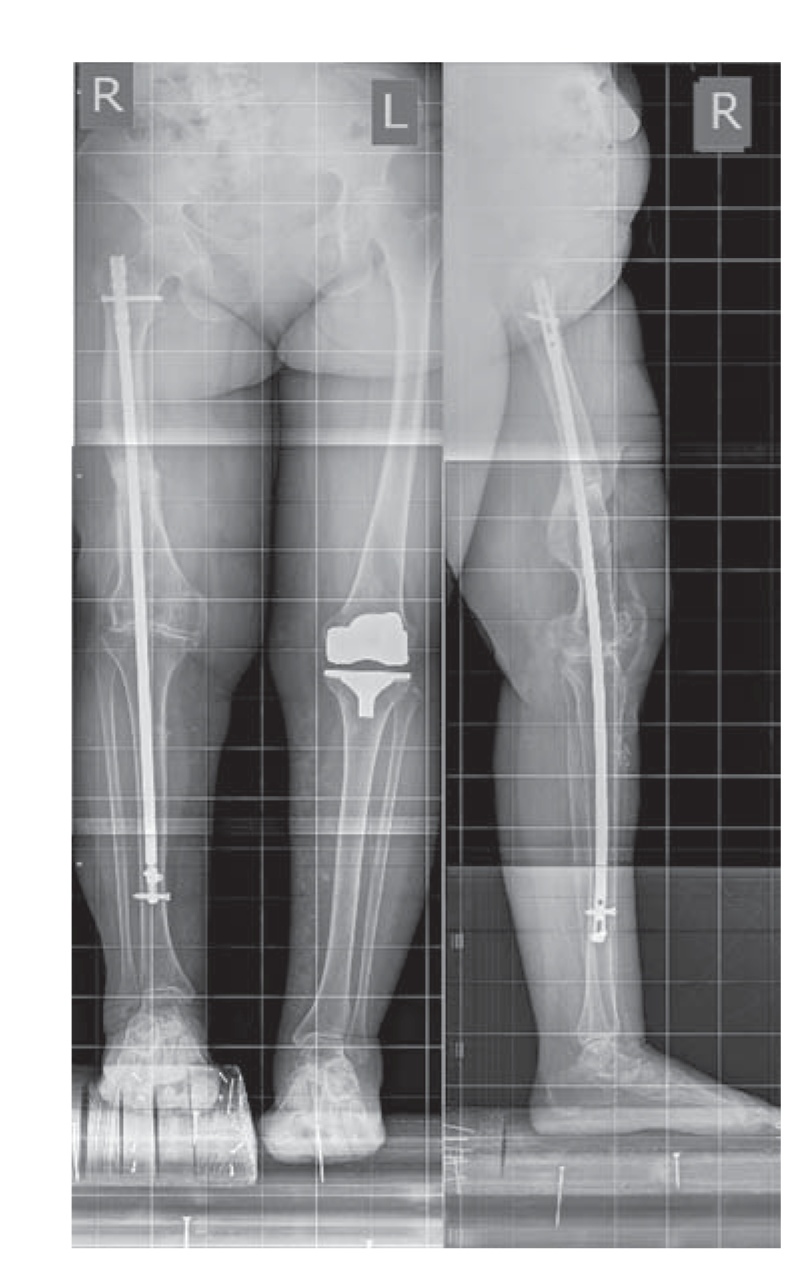

Пациентка А., 56 лет, поступила в клинику ФГБУ «РНИИТО им. Р.Р. Вредена» (далее РНИИТО) 21.04.2017 с диагнозом: консолидированный с варусной и торсионной посттравматической деформацией (перелом диафиза в средней трети) правой бедренной кости посттравматический гонартроз III стадии, болевой синдром, фиброзный анкилоз правого коленного сустава, укорочение правой нижней конечности 5 см (рис. 1). Пациентка была направлена в РНИИТО из региона Российской Федерации для госпитализации с целью получения высокотехнологичной медицинской хирургической помощи.

Рис. 1. Телерентгенограммы обеих нижних конечностей пациентки до операции.

Fig. 1. Long leg films of both lower extremities of the patient before the surgery.

По телерентгенограммам обеих нижних конечностей и рентгенограммам коленного сустава были оценены характер и величина имеющейся деформации правой нижней конечности во фронтальной и сагиттальной плоскостях (23° варусной деформации, 9° антекурвационной деформации). Были зарегистрированы изменения, характерные для посттравматического гонартроза III стадии с преимущественным поражением медиального отдела коленного сустава: значительное сужение суставной щели (по типу «кость на кость»), выраженные костные разрастания по краю мыщелков бедренной и большеберцовой костей, латеральный подвывих голени, признаки пателлофеморального артроза. По данным компьютерной томографии была выявлена наружная торсия бедренной кости 15° на уровне консолидированного с деформацией перелома. По результатам лабораторных исследований признаков системного воспаления у пациентки не было обнаружено.

Рис. 5. Телерентгенограммы пациентки в прямой и боковой проекциях после операции.

Fig. 5. AP and lateral long-leg films of the patient after the surgery.